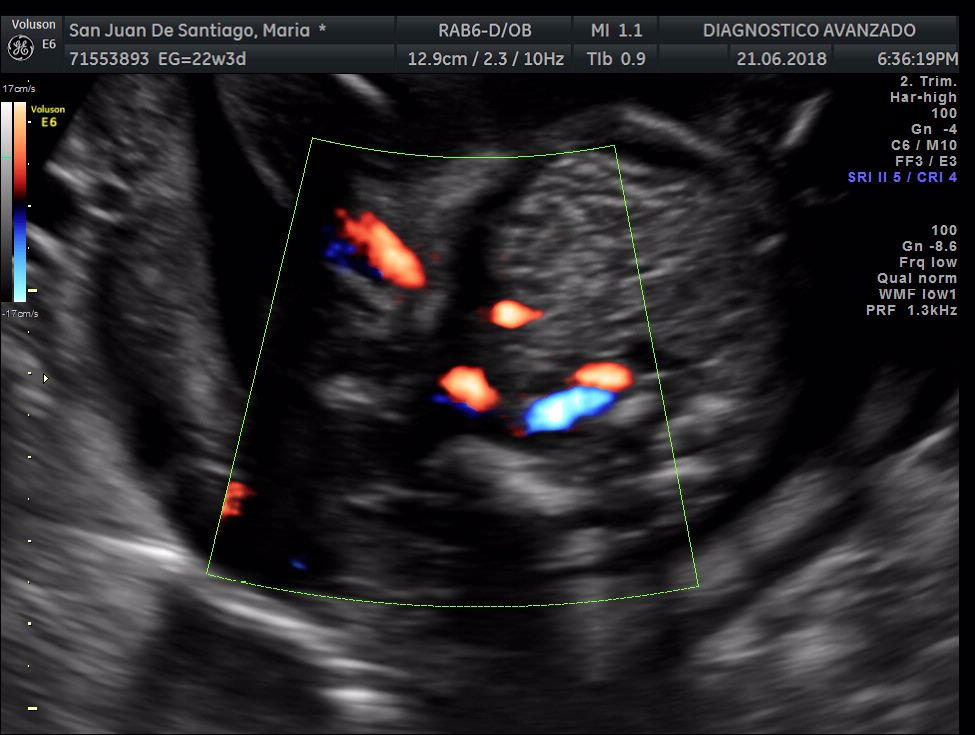

¡Hola a todos! Hoy hemos ido a hacer la tradicional ecografía 3D de la niña, os dejamos todo el material (aunque es un poco demasiado).